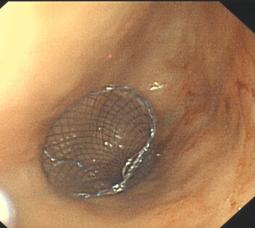

4. 食管、结肠支架置放:食道癌、结肠癌晚期失去手术机会或有手术禁忌症者,食管气管瘘等;

幽门恶性梗阻金属支架置放